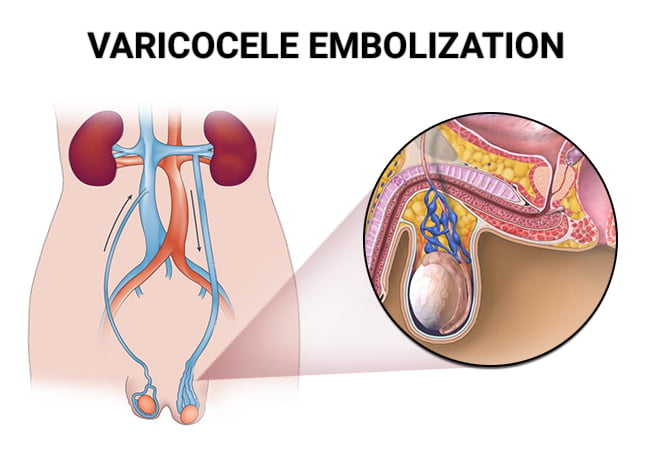

Varicocele Embolization